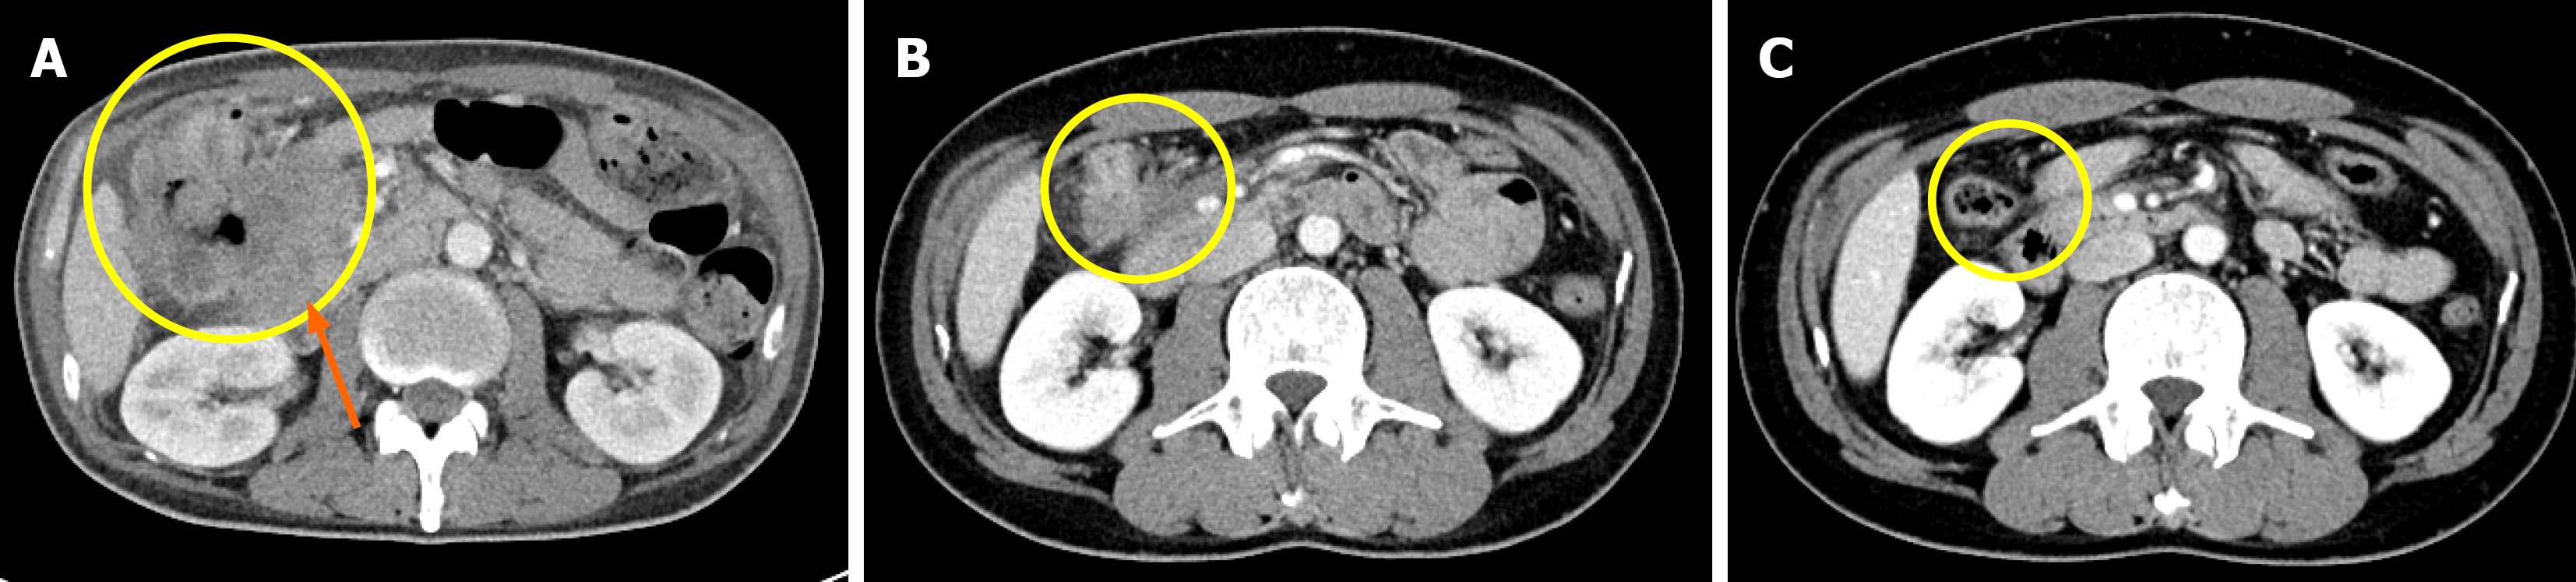

Figure 2 Colonoscopy performed after receiving immunotherapy for 17 months.

The scope was inserted through the anus and advanced to the transverse colon, but further passage was not possible due to luminal obstruction at the tumor site.